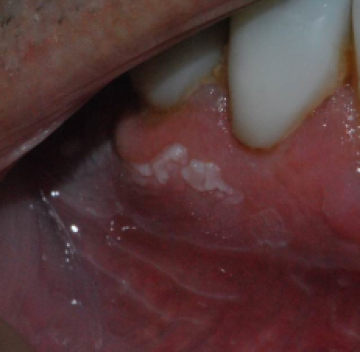

Diagnose à vue

Poll witte vlek op het tandvlees

© Maurice Sterckx

Week 44

31 okt 2016

Een 70-jarige man presenteert zich met een witte vlek onder op het tandvlees.

Hij heeft geen pijn, maar de vlek is ook niet weg te poetsen. Wat is uw diagnose?